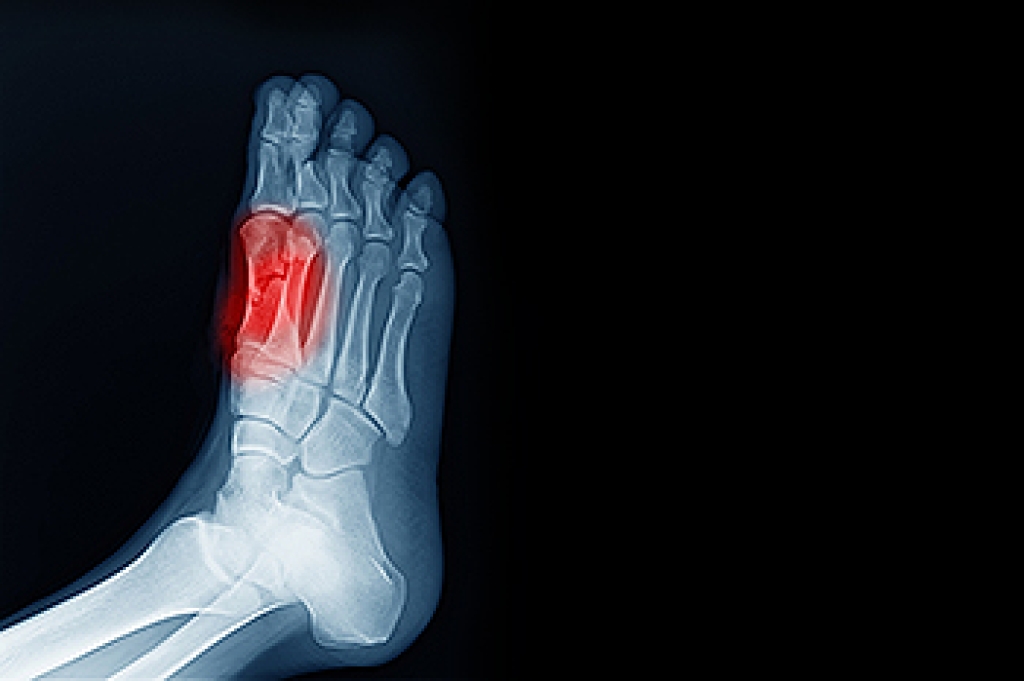

Pain under the big toe can be linked to irritation of the sesamoid bones, two small, round bones located beneath the big toe joint. These bones sit inside a tendon, a strong band of tissue that helps bend the toe. They act like shock absorbers and help support body weight when walking and running. Repetitive pressure from high-impact sports, wearing tight shoes, foot injuries, or certain foot structures can lead to inflammation in this area, known as sesamoiditis. People may notice aching, swelling, tenderness, or difficulty pushing off while walking. Pain may develop gradually and worsen with activity or when wearing shoes that press on the ball of the foot. A podiatrist can examine foot movement and order imaging tests to confirm the cause of pain. Treatment options include footwear guidance, protective padding, and custom orthotics to reduce pressure. If you have pain under the big toe, it is suggested that you make an appointment with a podiatrist for an exam, diagnosis, and treatment.

Sesamoiditis is a condition of the foot that affects the ball of the foot. It is more common in younger people than it is in older people. It can also occur with people who have begun a new exercise program, since their bodies are adjusting to the new physical regimen. Pain may also be caused by the inflammation of tendons surrounding the bones. It is important to seek treatment in its early stages because if you ignore the pain, this condition can lead to more serious problems such as severe irritation and bone fractures.